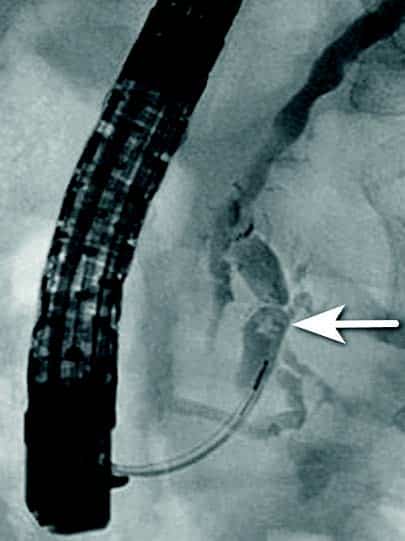

Obstruksjon av gallegang

Inflammasjon og fibrose i caput av pankreas kan skade gallegang og føre til benigne strikturer og kolestase. Slike strikturer kan være krevende å behandle. Det er viktig med god bildediagnostikk i forkant av terapi for å utelukke malign striktur, noe som kan være vanskelig på grunn av de inflammatoriske/fibrotiske forandringene sekundært til kronisk pankreatitt. Det er svært viktig at man ikke intervenerer endoskopisk dersom usikkerhet om malign etiologi men henviser til senter med HPB kirurg og MDT vurdering. Standard behandling av benigne strikturer har vært ERCP med gjentatte dilatasjoner og innleggelse av multiple plaststenter i gallegang over en periode på ett år (Fig 5). De senere år har bruk av selvekspanderende metallstent i 6-12 mnd. blitt mer vanlig dersom forholdene teknisk ligger til rette for dette. Det er imidlertid risiko for residiv av striktur på grunn av progresjon av grunntilstanden så gjentatt endoskopisk behandling kan bli nødvendig.

Fig 5: Pasient med gallegangsstriktur sekundært til kronisk pankreatitt som behandles med endoskopisk ballong dilatasjon og stenting av gallegang.